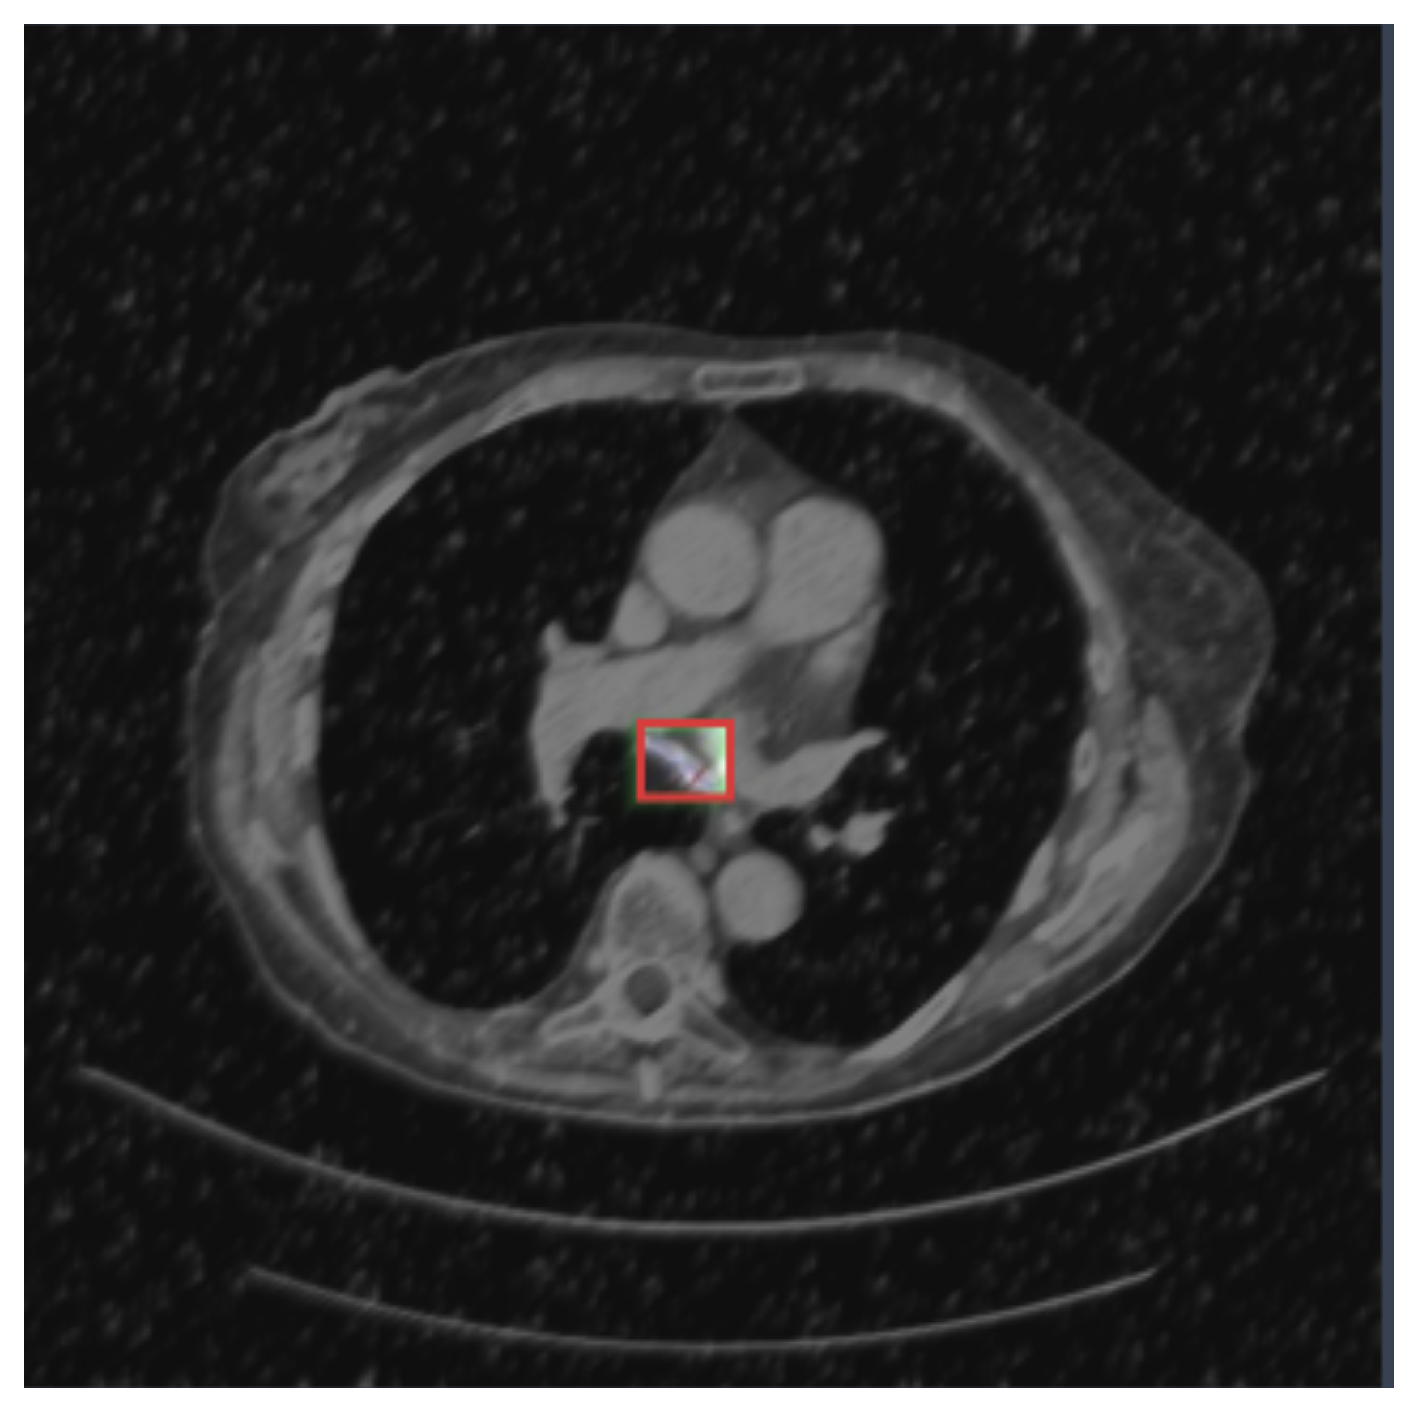

4. Experimental Analysis